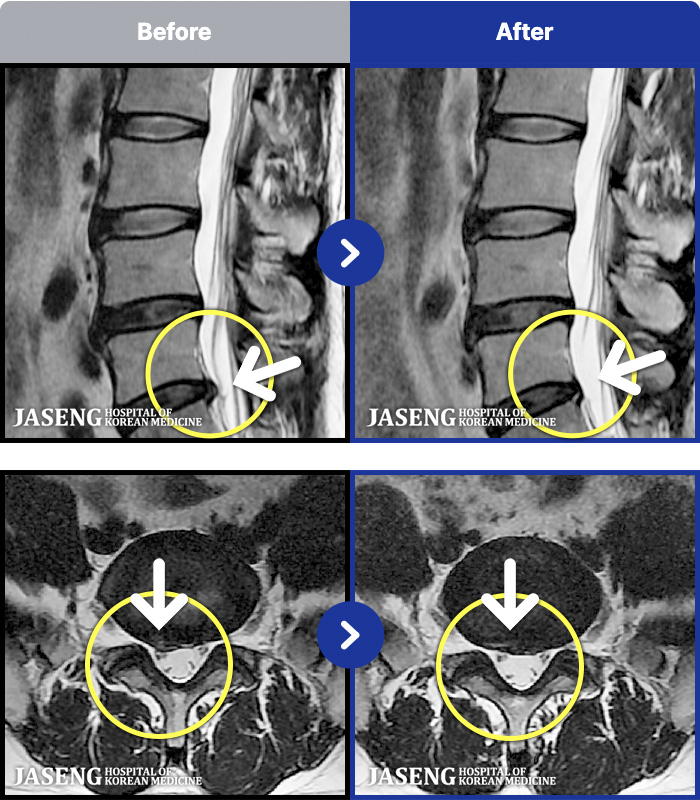

54 MRI ũ ʸ Ȯϼ.

ȯںп Ǹ ǿ ԿǾ, ο ġ ۿ Ƿ ġḦ Ͻñ ٶϴ.